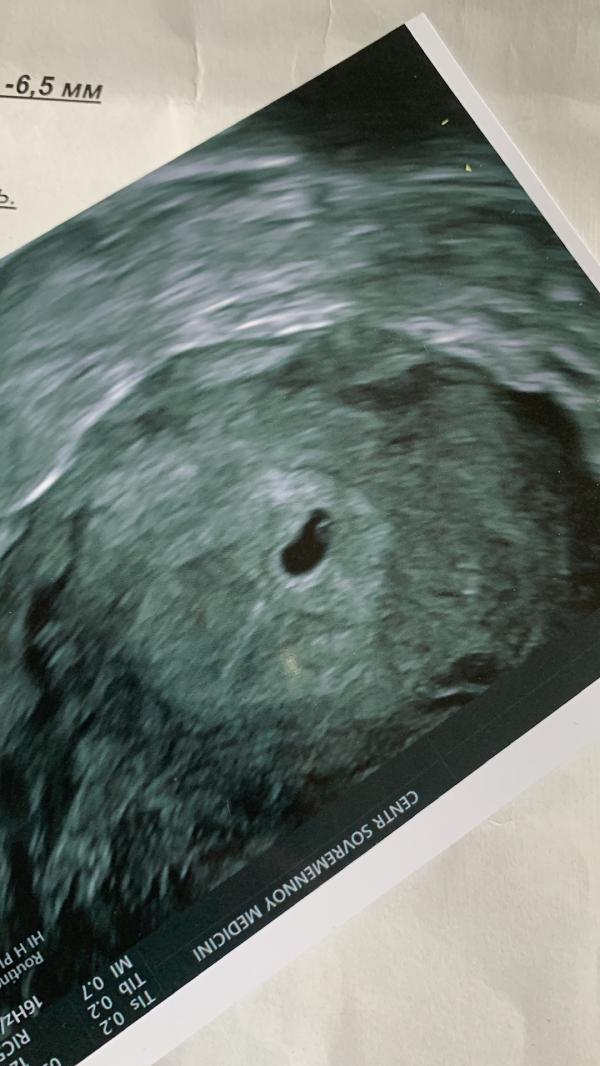

Прикрепила фото узи на 5 недель, ходила на подтверждение беременности, все на месте🥹😁🤍

Сейчас нам уже 10,3🥰